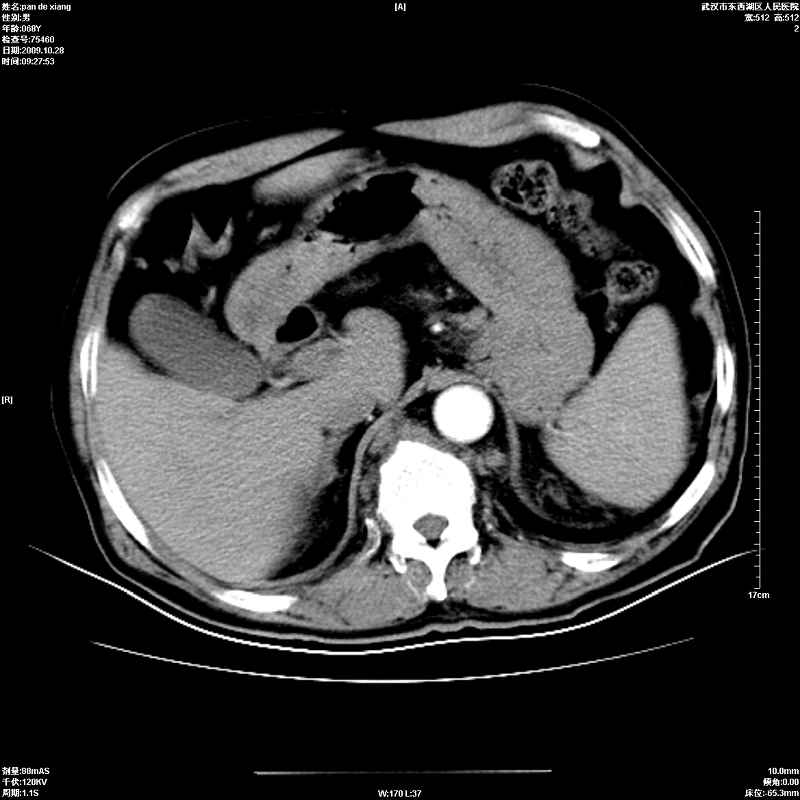

以下是引用杀毒软件在2009-10-28 20:41:00的发言:[br]结合临床考虑---白血病双肾改变或淋巴瘤。

以下是引用zxl51642在2009-10-29 9:59:00的发言:[br]结合临床“单克隆免疫球蛋白血症”,考虑双肾为继发损害并肾功能不全(尿中大量igg及少量iga、igm等大分子免疫球蛋白滤出所致继发损害),椎前软组织肿块为髓外造血。与浆细胞瘤有区别,平扫时有战友说的很清楚。